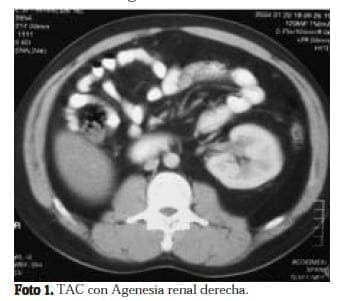

Varón de 37 años, quien consultó al servicio de urgencias por orquialgia derecha. Al examen físico se anotaba masa palpable a nivel del polo superior del testículo derecho dolorosa, mal definida. Con sospecha de neoplasia testicular, se solicitaron estudios de extensión y se llevó el paciente a orquidectomía radical derecha. El reporte de patología fue de isquemia testicular. Sin embargo, en la tomografía se reporta la presencia de una masa retrovesical y agenesia renal derecha. Como hallazgo incidental (Fotos 1 y 2). Los radiólogos recomiendan realizar resonancia magnética nuclear para aclarar el diagnóstico.

La resonancia muestra una masa multiloculada (foto 3 y 4) dependiente de la vesícula seminal derecha y agenesia renal ipsilateral. Se realizó además una ecografía transrectal de próstata, donde se identificó una gran masa quística que rechaza la pared posterior de la vejiga.